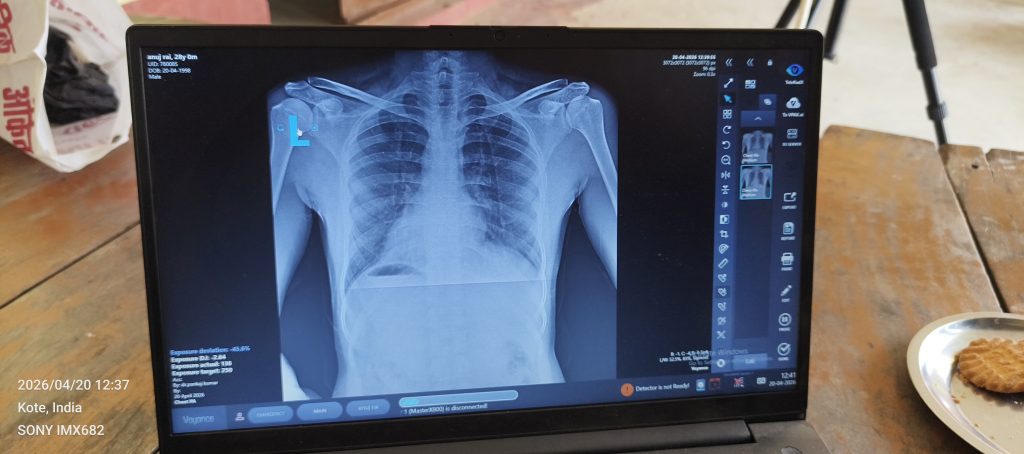

बलिया : ‘टीबी मुक्त भारत अभियान’ को गति देते हुए आज जिला क्षय रोग अधिकारी डॉ. साकेत बिहारी के कुशल मार्गदर्शन में ग्राम सभा अजोरपुर के भिखारीपुर गांव में विशेष स्वास्थ्य शिविर का आयोजन किया गया। इस शिविर का मुख्य फोकस उच्च जोखिम वाली जनसंख्या (High Risk Population) की पहचान कर उनका डिजिटल एक्स-रे परीक्षण करना रहा।

अभियान के दौरान अपनी बात रखते हुए कोऑर्डिनेटर अनुराग पांडेय ने कहा, “हमारा उद्देश्य केवल जांच करना नहीं, बल्कि हर उस व्यक्ति तक पहुंचना है जो इस बीमारी के प्रति संवेदनशील है। जिला क्षय रोग अधिकारी के निर्देशानुसार हम गांव-गांव जाकर लोगों को प्रेरित कर रहे हैं ताकि कोई भी लक्षित व्यक्ति जांच से छूट न जाए। समय पर जांच ही टीबी को जड़ से मिटाने की पहली कड़ी है।”

डिस्ट्रिक्ट कोऑर्डिनेटर आशीष सिंह ने बताया कि विभाग का लक्ष्य क्षेत्र की समस्त लक्षित जनसंख्या की शत-प्रतिशत जांच सुनिश्चित करना है। शिविर के दौरान सुमित कुमार (Vaina) ने भी सक्रिय भूमिका निभाई और स्थानीय निवासियों को टीबी के लक्षणों एवं बचाव के प्रति जागरूक किया।